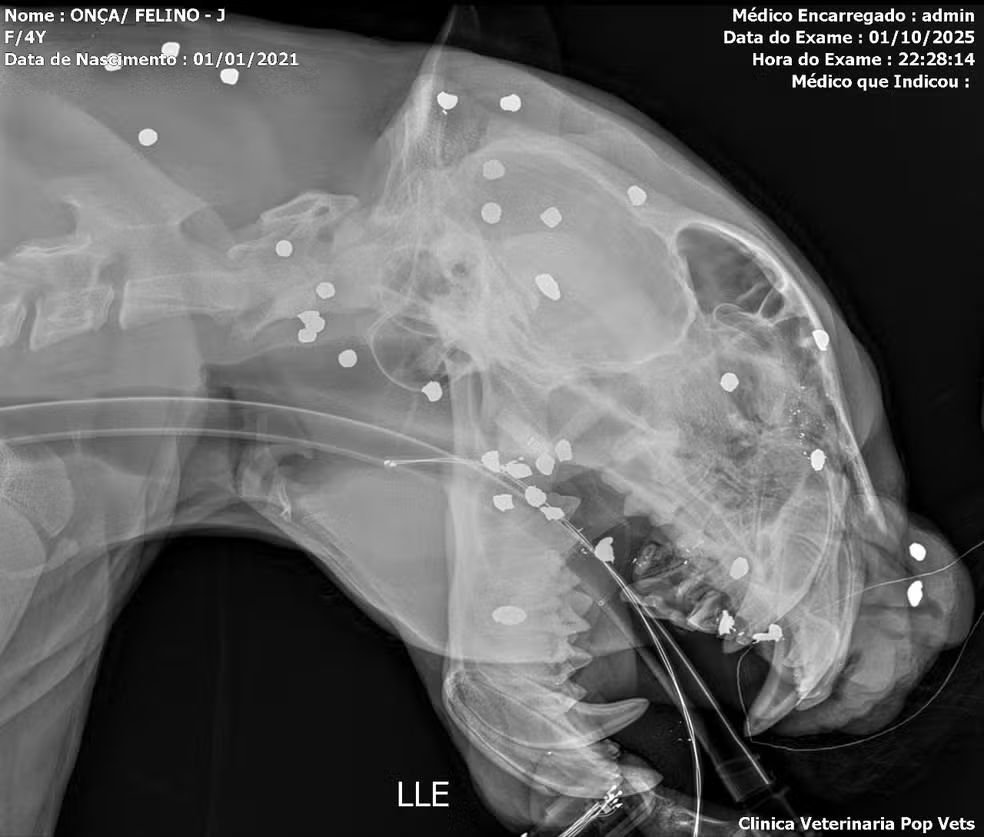

Redação – Um exame de raio-X feito após o resgate de uma onça-pintada nas águas do Rio Negro, em Manaus, mostrou que o animal foi atingido por mais de 30 estilhaços de tiro pelo rosto, cabeça e pescoço. A informação foi divulgada pela equipe de veterinários que presta assistência ao animal nesta quinta-feira (2).

Segundo a equipe que cuida do animal, além dos estilhaços causados por um tiro por arma de caça que levou na cabeça, a onça estava com dentes quebrados, ferimentos visíveis na cabeça e com debilidade intensa.

“A gente percebe que o tiro ele foi executado a distância. Ficou muito espalhado, não ficou um tiro concentrado em uma região. Se tivesse sido concentrado, o animal com certeza teria vindo a óbito. Então, a gente percebe que a pessoa deve ter atirado de longe, afim de fazer um afugentamento. Um tiro desse tipo no rosto, uma região extremamente sensível tem que ser avaliado de forma muito profunda”, explicou o biólogo e pesquisdor em felinos, Rogério Fonseca.